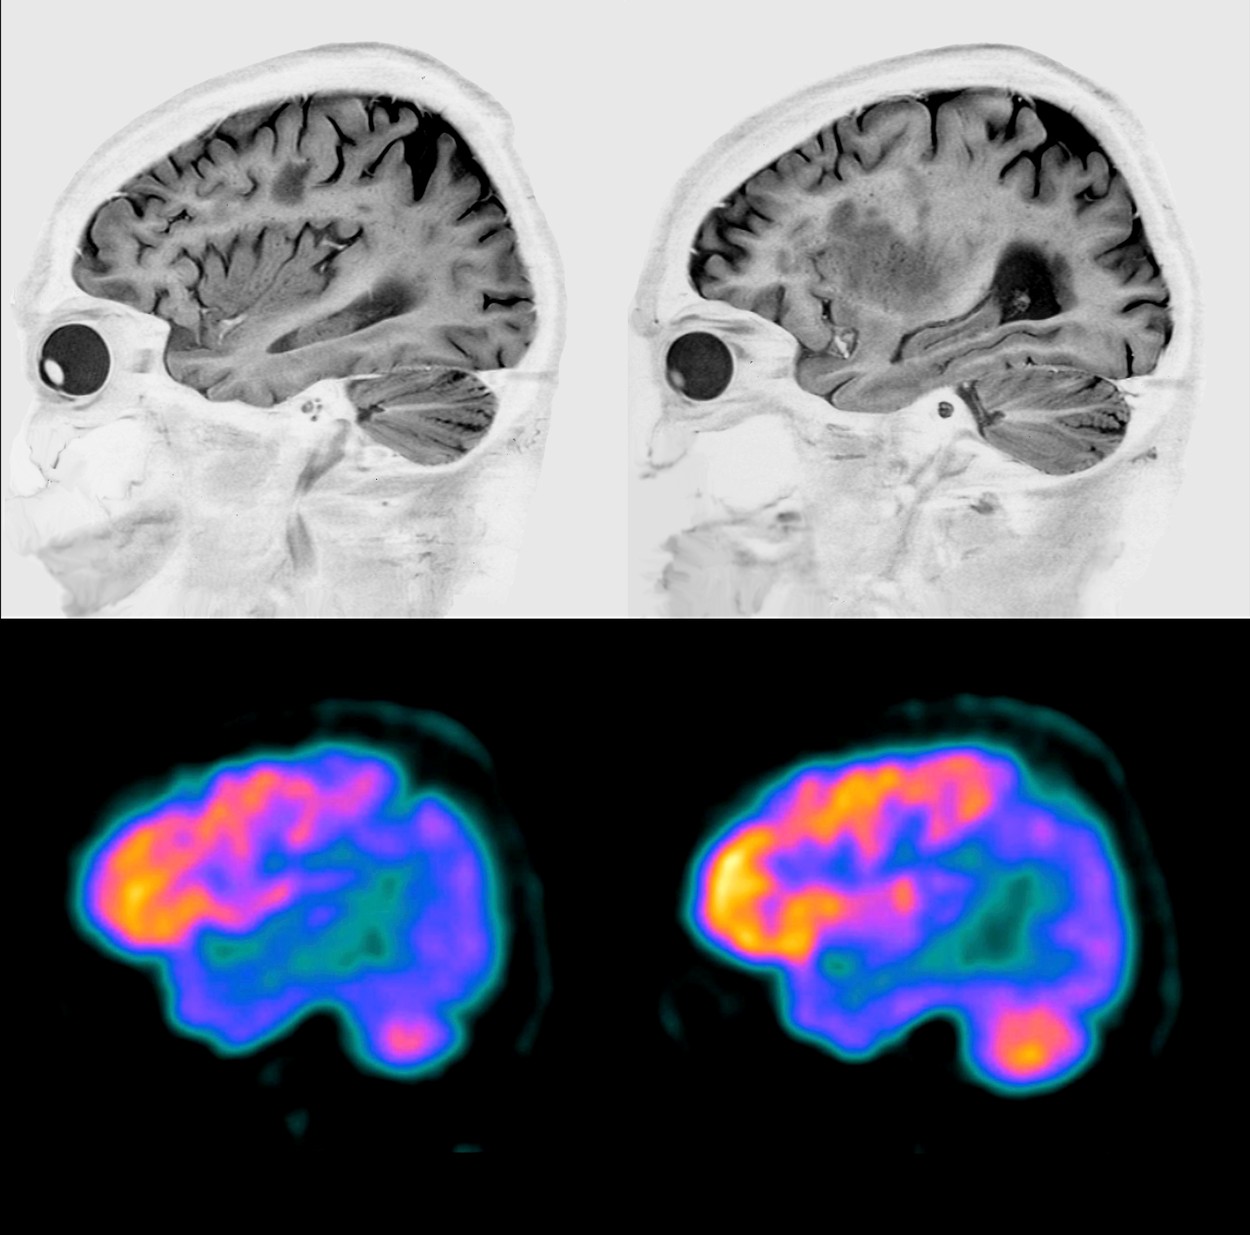

Različne nevrodegenerativne bolezni prizadenejo različne predele možganov. V zadnjih letih je tehnologija slikanja možganov zelo napredovala. Tako lahko zdravniki s pomočjo metod, kakršni sta funkcijska magnetna resonanca (MRI) in pozitronska emisijska tomografija z radioaktivno 18F-fluordeoksiglukozo (FDG PET), pri bolniku prepoznajo za neko bolezen značilen "možganski zemljevid". Nenormalnosti možganskega omrežja je pogosto mogoče prepoznati celo že pred pojavom simptomov, podatke pa uporabiti najprej za diagnosticiranje in nato za spremljanje napredovanja bolezni.

Pri slikanju FDG PET bolniku v veno vbrizgajo radioaktivno označeno glukozo, ki se razporedi po presnovno aktivnih organih. Velik del je privzamejo možgani. Radioaktivni elementi pri razpadu oddajajo sevanje, ki ga zaznajo s posebno kamero PET, in tako zdravniki ocenijo, kateri predeli možganov so bolj, kateri pa manj aktivni. Pri zdravem človeku je razporeditev radioaktivne glukoze enakomerna v celotni možganski skorji in globokih možganskih jedrih. Pri bolnikih z nevrodegenerativnimi boleznimi pa je razporeditev glukoze specifično spremenjena. Z osnovnim pregledom slik FDG PET lahko prepoznajo predele s spremenjeno aktivnostjo, z naprednimi analitičnimi modeli pa lahko ocenijo, kako so ti predeli združeni v omrežja.